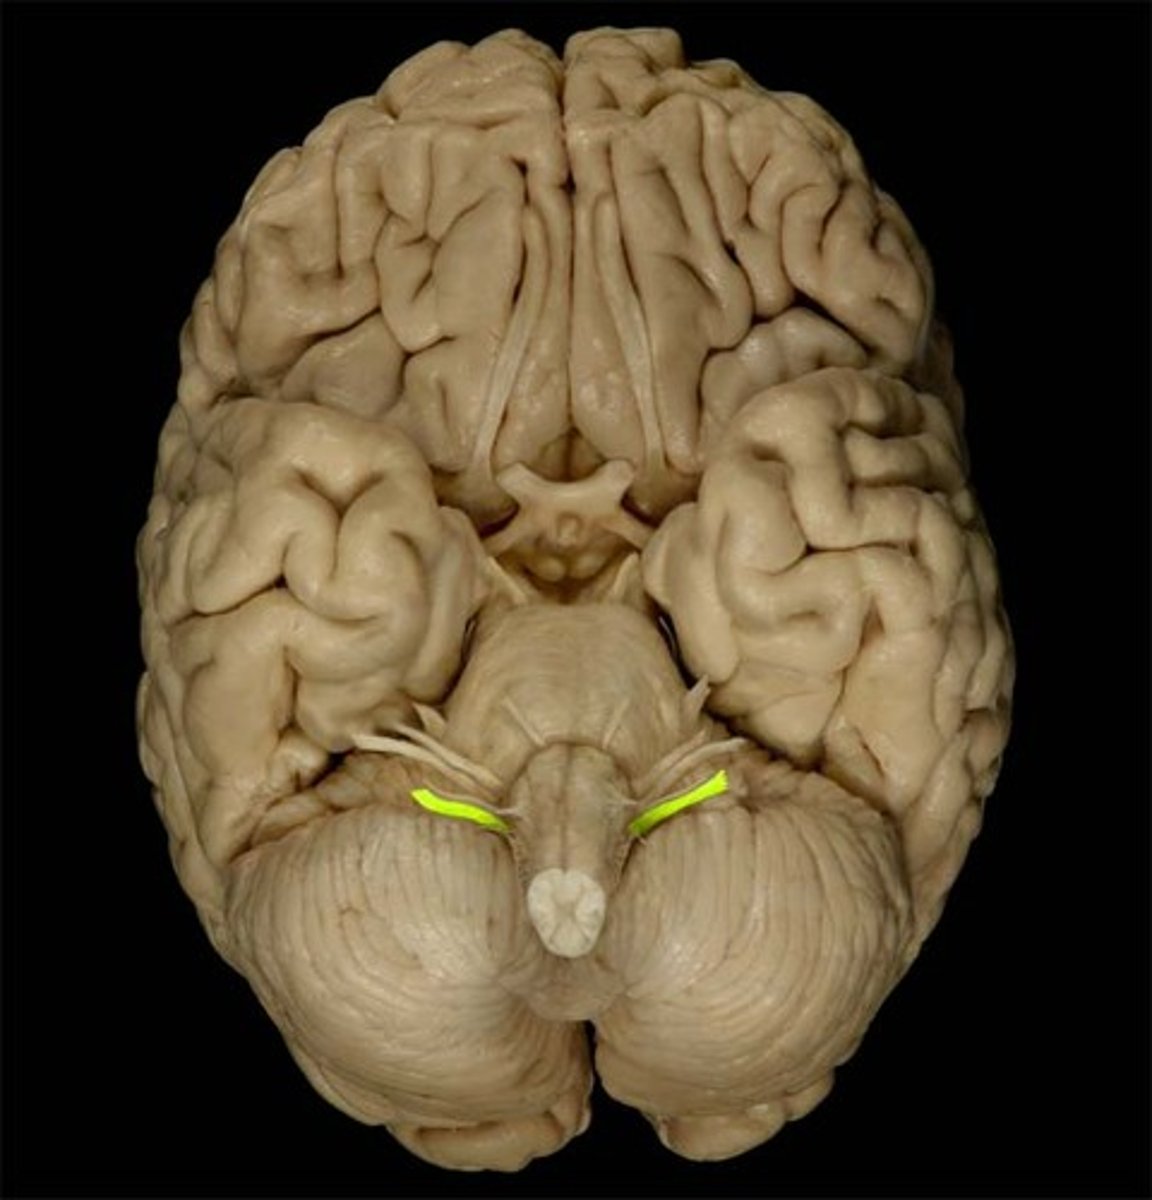

Medulla oblongata

Glossopharyngeal nerve (CN IX)